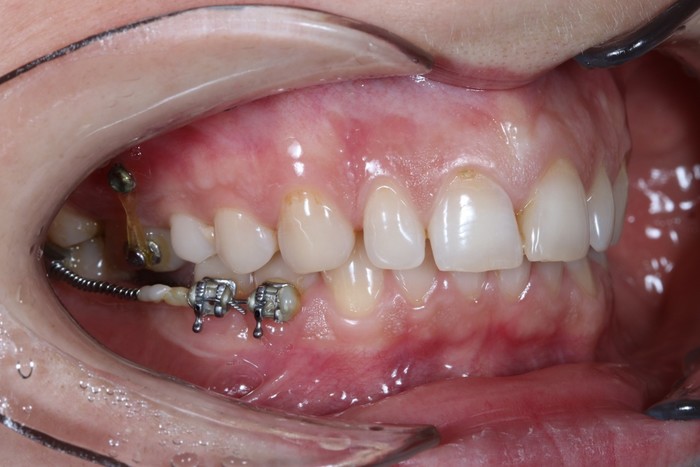

Константин пунктуально прибыл в намеченный день и час. 3 июня 2023. Осмотрев полость рта и «заколдованное» место, в частности, я предложил начать. Константин согласился, хоть и немного волновался. Но это и немудрено после всего того, что он прошёл.

Конечно, меня посещали мысли, что же там такого, что первый раз почти 6 часов пытались удалить зуб, а во второй вообще ёбанули нерв. Сделал анестезию, разрез, и удалил зуб за 4 минуты.

Уточняю: 3 минуты ждали, пока подействует анестезия, 4 минуты удаляли зуб, 5 минут накладывали швы, 3 минуты я катал Константина в кресле вверх и вниз. Всё. Меньше 15 минут ушло на удаление остатков зуба мудрости. На целый ушло бы не больше 25.

Белые точки – это остатки йода от йодоформной турунды, которую уложили в больнице (если вы читали выписку). Он рентгеноконтрастен.